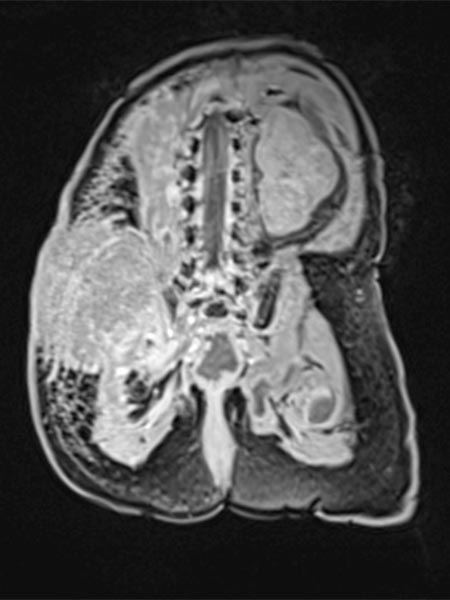

Native T1-weighted MRI shows the tumor to be hypointense. The tumor has blurred margins. The surrounding adipose tissue is saturated with lymphedema.

In corresponding T2-weighted, fat-saturated MRI, the tumor shows hypointense parts (hemorrhages), but also hyperintense parts and is overall very inhomogeneous and blurred. The surrounding fat tissue is saturated with lymphedema.

This surrounding subcutaneous lymphedema (hyperintense in axial T2-weighted, fat-saturated MRI ) is a typical feature of kaposiform hemangioendothelioma and also extends significantly in the surrounding area.